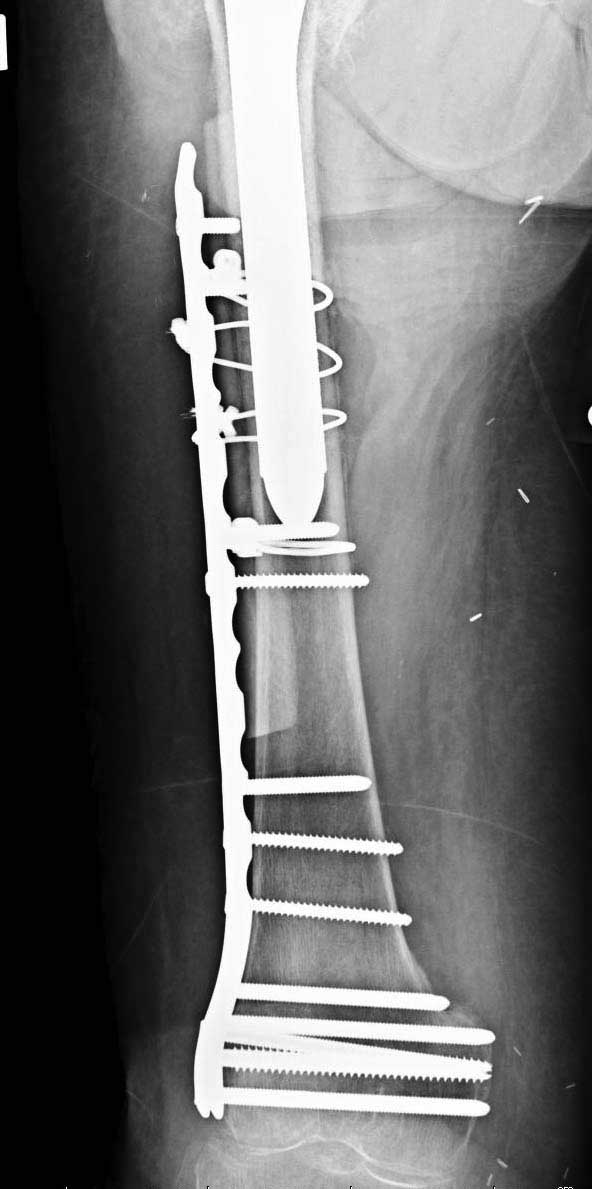

Обычно после чрезвертельных переломов, за исключением молодых, у пожилых остается нестабильность при движении. Часто падают и после 3х мес. в результате падения обнаружен перипротезный перелом (22-23), который зафиксирован Синтез пластиной.

Повторно поступает после двух с половиной лет, где обнаруживается перелом на второй стороне. Немного сложно, но для фиксации выбрали Antegrade InterTan Smith Nephew Nail и с момента фиксации более 3х мес.